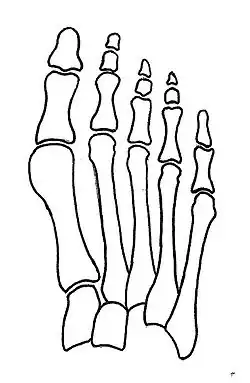

Normal foot skeleton

Fig 1a: Normal foot skeleton

First metatarsal bone has moved aside

Fig. 1b: First metatarsal bone has moved aside

Primus varus deformity is the leaning of the first metatarsal bone away from the second metatarsal and towards the opposite foot (Fig. 1). As it leans over, its head sticks out to form the bunion bump and it also widens the forefoot to cause shoes feeling too tight. Thus when bunion pain becomes unmanageable, surgical correction is to narrow the forefoot by repositioning of the first metatarsal head back to its normal position. This can be done by osteotomy (bone-breaking), soft tissue (non-osteotomy) or fusion techniques.